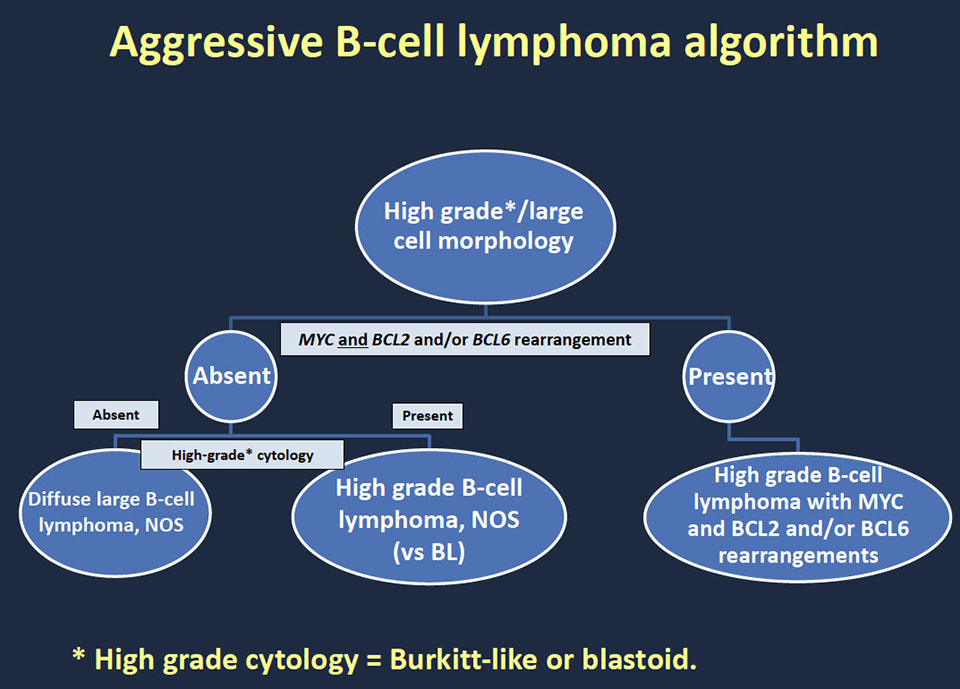

High-grade B-cell lymphoma

- High-grade B-cell lymphoma with MYC and BCL2 and/or BCL6 rearrangements

- High-grade B-cell lymphoma, NOS